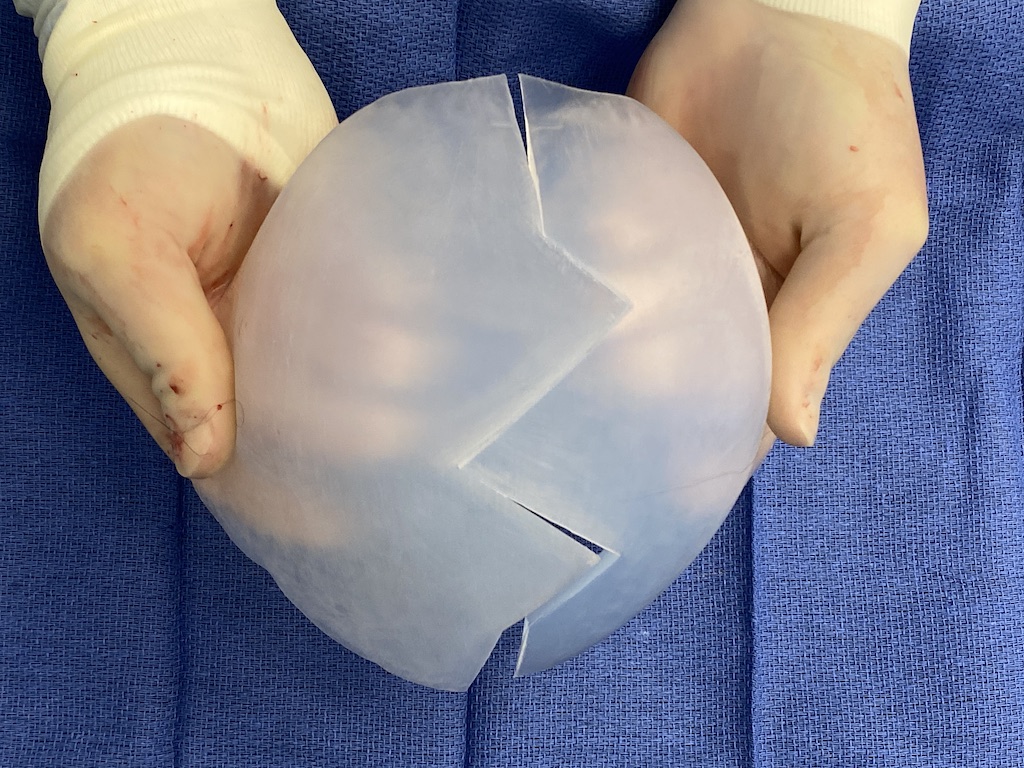

Desire for major head reshaping with a taler and wider head shape.

Placement of large two piece custom skull implant through a sagittal scalp incision.

Desire for major head reshaping with a taler and wider head shape.

Placement of large two piece custom skull implant through a sagittal scalp incision.